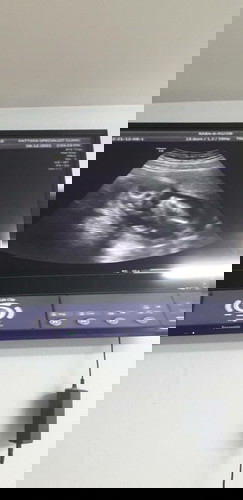

เบบี๋ 14 วิค

ขอดูเบบี๋ของแม่ๆหน่อยค่ะ กำหนดคลอด 8 มิ.ย. 65